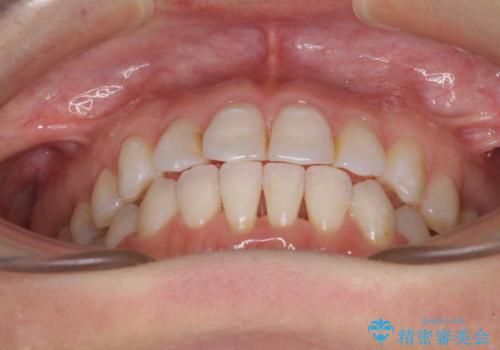

長年気にしていた前歯 インビザラインで目立たず改善

- ワイヤーではない矯正治療があると聞いたとのことで来院された患者様です。

長年前歯のデコボコを気にしていたもののワイヤー矯正に抵抗があり躊躇していたそうですが、インビザラインなら治療してみたいとのことで相談にいらっしゃいました。

インビザライン適用の歯列であったため、歯と歯の間を削るIPRを用いて改善することとしました。

下顎前歯の叢生が顕著な場合、歯列改善後に歯と歯と歯肉の間にブラックトライアングルという隙間ができてしまいます。

軽減することはできますが、完全に解決することは矯正治療のみでは不可能なため、リスクとして事前に周知しておく必要があります。